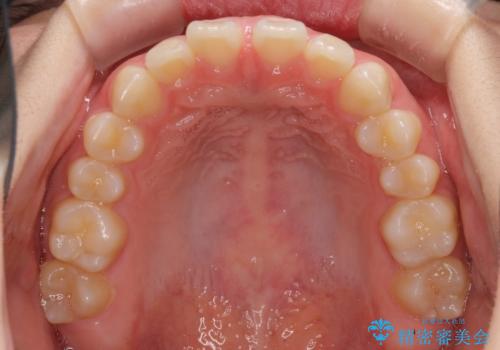

- 上の前歯の隙間を気にして来院された患者様です。

インビザラインにより、隙間を閉じながら、隙間の原因であるディープバイトを改善していくこととしました。

下顎の歯列が強く上顎に咬みこむことで隙間ができてしまうため、マウスピースの保定装置では後戻りのリスクが高くなってしまいます。

そのため、上下ともに前歯の裏側を細いワイヤーで固定し、その上から保定装置のマウスピースを使用していただくこととしました。